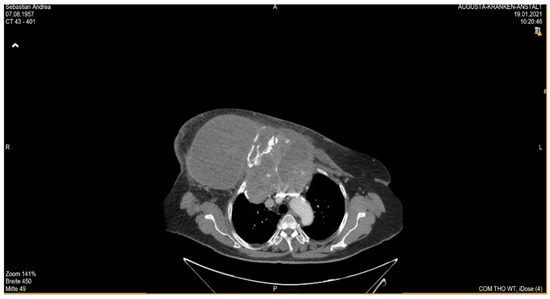

She returned to Bochum in June 2018 with the following symptoms: on the right ventral chest wall, she had a large tumor with a perforation in the pericardium of approximately 15 × 20 cm, an abdominal inguinal tumor on the right, and an ulcerating tumor on the lower left side of the abdomen. A computed tomography of the thorax and abdomen was performed in 09/2018 (Figure 2 and Figure 3) and a magnetic resonance imaging of the thorax was performed in 06/2018 (Figure 4 and Figure 5).

Figure 2.

Computed tomography of thorax and abdomen (CT Thx/Abd) in 2018. In this study, we detected a large tumor on the right anterior thorax with calcifications and invasion in the mediastinum.

Figure 3.

Computed tomography of the thorax and abdomen (CT Thx/Abd) in 2018. There is a large, partially calcified soft tissue structure of the right breast with central hypodensity and possibly mucinous parts. The image shows infiltration of the thoracic wall and transfer to the mediastinum, with destruction of the corpus and manubrium sterni and infiltration of the musculus pecotralis major and the musculus serratus anterior on the right. Additionally, destruction of the adjacent medial clavicle on the right and of the first rib medial on the right was observed. The formation directly infiltrates the mediastinum, with infiltration of the pericardium and direct contact with the aortic arch. The maximum extent of this conglomerate was 25.2 × 14.8 × 10.0 cm (VU 22.7 × 16.6 cm axial; not fully recorded cranially). There was no flow obstruction of the right-side vessels of the upper thoracic aperture.